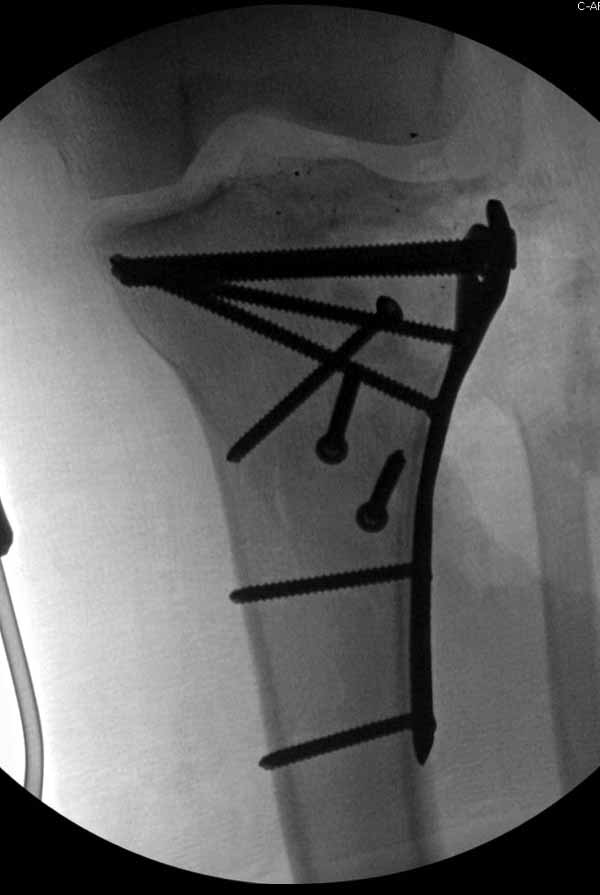

Из всех перечисленных методов подходит вариант пластики аутокостью и усиление (арматура) шурупами. Основная задача сохранить интактную медиальную стенку и латеральный кортекс. Доступ передне-латеральный, но надо работать спереди шейки через небольшое окно в 10-15 мм. Фиксацию надо проводить между медиальной тонкой стенкой головки и латеральным кортексом. Каннюлированные шурупы 6.5 мм очень грубые и могут разрушить остаток стенки. Фиксировать надо кортикальными шурупами 3.5 мм, которые создадут мостик и арматуру в шейке. Провести по периметру шейки 4, и в центре пару шурупов. Во время операции и при манипуляции соблюдать осторожность, в любой момент может наступить стресс перелом. Заранее надо заказывать длинные шурупы!